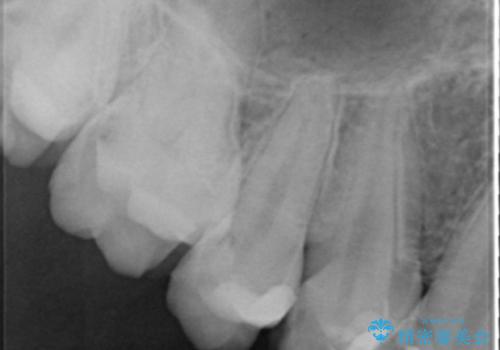

下顎の埋伏していた親知らずも抜去しました。